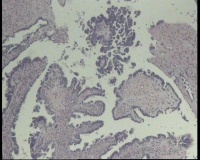

求会诊!左侧卵巢囊肿,够交界性浆液性囊腺瘤吗?

左侧卵巢囊肿大小约6.5x6.0厘米

碎囊壁组织5.0厘米一堆,壁厚0.1—0.4厘米,局灶囊壁见散在赘生物0.3,0.5厘米。另见完整小囊肿1.5x1.0厘米,无内容物,壁厚0.1厘米,内壁附0.8x0.7x0.4厘米赘生物,颗粒状

交界性浆液性乳头状囊腺瘤